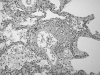

Talc induced pulmonary granulomatosis